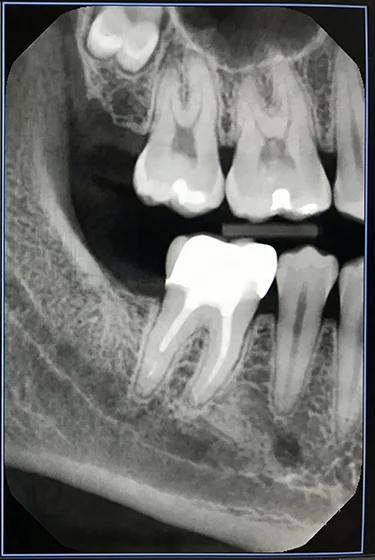

Brush twice a day with fluoridated toothpaste and floss gently around the filled tooth to limit plaque buildup. Avoid chewing ice or hard candies, and reduce sugary snacks to lower the risk of new decay around the filling. If sensitivity lasts or you notice a crack, contact us promptly. With steady care, dental fillings can last for many years.